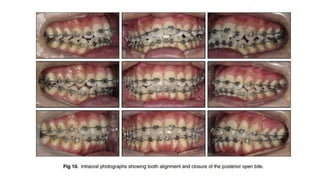

• The posttreatment photographs and radiographs showed that facial symmetry and an ideal occlusion

with proper overjet and overbite were achieved.

• The mandibular dental midline coincided with the facial and maxillary midlines, and the occlusion

was finished to Angle Class I canine and molar relationships.

• The panoramic radiograph showed that new bone with the same characteristics as adjacent bone was

created on the affected side by gradual separation of the 2 bony segments that were surgically severed

• Superimposition of 3-dimensional computed tomographs showed that after distraction osteogenesis

and the consolidation phase, the shorter ramus was lengthened to 54.5 mm, the mandible was

advanced compared with pretreatment, and the ANB angle decreased to 2.3.

• However, the overall superimposition showed that some relapse occurred during orthodontic

treatment: an ANB angle of 4.3 and ramus height of 53.0 mm were observed at the end of treatment.

• At 1 year after debond, the results were stable, and the patient was satisfied with his facial esthetics.